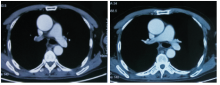

郑明英:患者在2014-10-24复查PET-CT示右肺动脉栓塞, 见图3; 放疗过程中出现频繁的恶心、呕吐, 伴咳嗽、咳痰, 查体:右下肺呼吸音减低, 11月28日复查胸部CT示:右侧胸腔积液较前增多, 左下肺出现斑片影; 胸腔积液找到腺癌细胞, 见图4。2014-11-28至2014-12-04 予抗感染治疗:头孢哌酮/舒巴坦 2.25g q8h, 2014-12-04复查胸部CT示左下肺斑片影无明显改变, 见图5; 请放射科医生重新评估胸部CT发现左肺动脉栓塞, 左下肺斑片影考虑肺栓塞造成。2014-12-12予患者GC方案化疗。